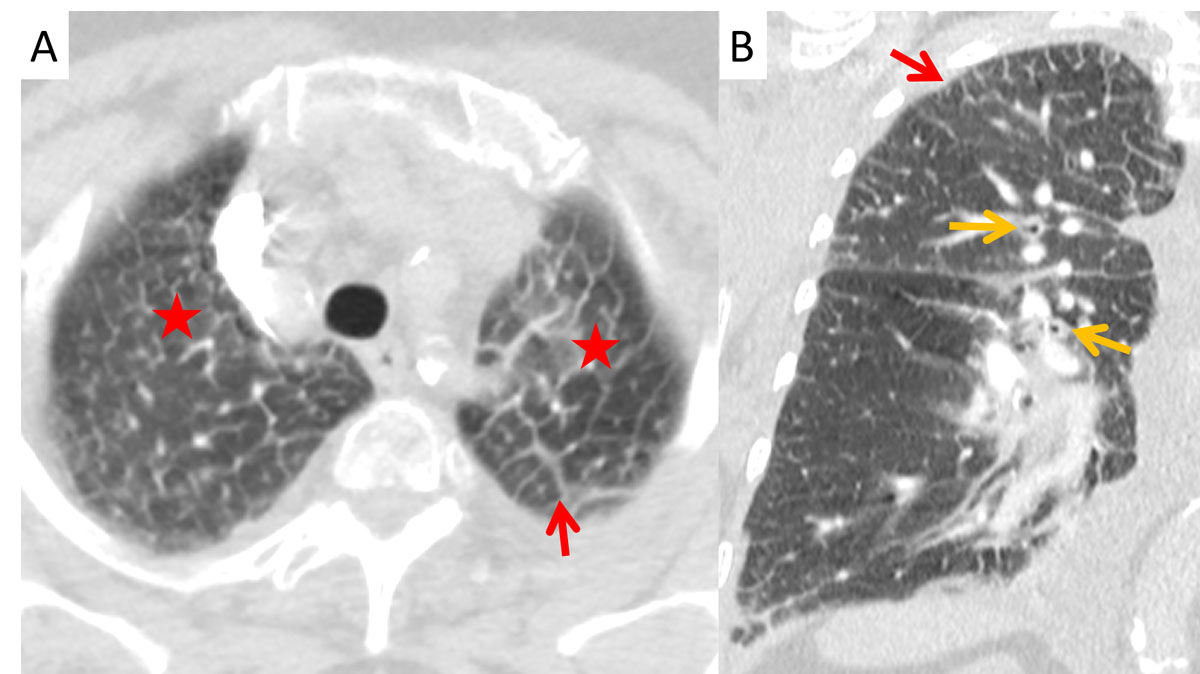

Interlobular septal thickening (IST) in the lung apex was present in of 81% and 76% of the cardiac and renal groups, respectively, which was significantly more than in the ILD group (26%, p <0.0001, figs 1–4 ). The distribution in the insufficiency group was more homogenous throughout the lungs than in the ILD group, in which the amount of septal thickening increased to 90% towards the lower lobes (table 2). The average thickness of the interlobular septa was rated between 1 and 2 with significantly thicker septal lines in the insufficiency group (1.45 ± 0.6) compared with the ILD group (1.28 ± 0.5; p <0.0001, fig. 3).

Figure 3 Interlobular septal thickening (orange arrows), slight architectural distortion (asterisks) and a faint honeycombing (red arrows) in a 70-year-old male patient with idiopathic pulmonary fibrosis (IPF).

Figure 4 Apical Kerley B lines (red arrows) in (A) axial and (B) coronal planes with peribronchial cuffing (orange arrows) and ground glass opacities (asterisk) from transudation in a 63-year-old male patient with renal insufficiency.

Peribronchial cuffing was significantly more often present in the cardiac than in the renal and ILD groups, in 67%, 29% and 12% of patients, respectively (p = 0.04 and p <0.0001). The average thickness of the bronchi did not differ significantly between the various groups, ranging from 1.27 to 1.4 (SD 0.5–0.8) with p-values >0.9 (fig. 4).

In this study, more than 80% of the patients with cardiac insufficiency and more than 70% of the patients with renal insufficiency presented with IST (Kerley B lines) in the lung apex. Miniati et al. described an identical distribution of the septal lines on conventional chest x-ray in the lower lungs among patients with heart or renal insufficiency [19]. While their distribution in the insufficiency group was homogenously throughout the lungs, the amount of Kerley B lines in our study increased to 90% towards the lower lobes in the ILD group. Findings of ILD predominate in the lung bases [8]. Patients with heart or renal insufficiency showed peribronchial cuffing due to increased capillary hydrostatic pressure or decreased oncotic pressure [1, 20]. One reason for the apical prevalence of the Kerley B lines in congested patients could be the redistribution of the pulmonary blood flow into the cranial parts of the lung, probably increasing the capillary pressure with resultant transudation. Kerley B lines are not a new sign in chest radiology, but their location in the lung apex is here described for the first time.